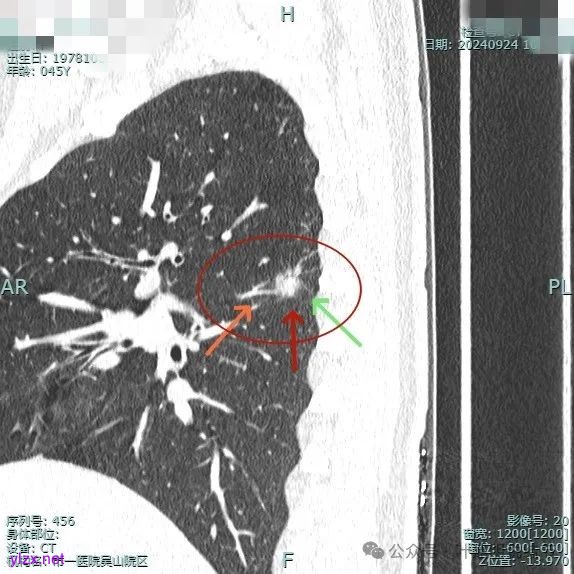

我们先来看2024年9月时的影像:

病灶1:

右下背段混合密度病灶,边上不太清爽,有片状淡磨玻璃影,实性部分密度较高。

感觉病灶有点晕征似的,表面不平,灶内不太致密。

有小血管进入,似有晕征。

离胸膜近但牵拉不明显,病灶边缘有细毛刺,较短且不太锐利。

边缘少许磨玻璃成分,血管进入明显。

瘤肺边界稍显不清。